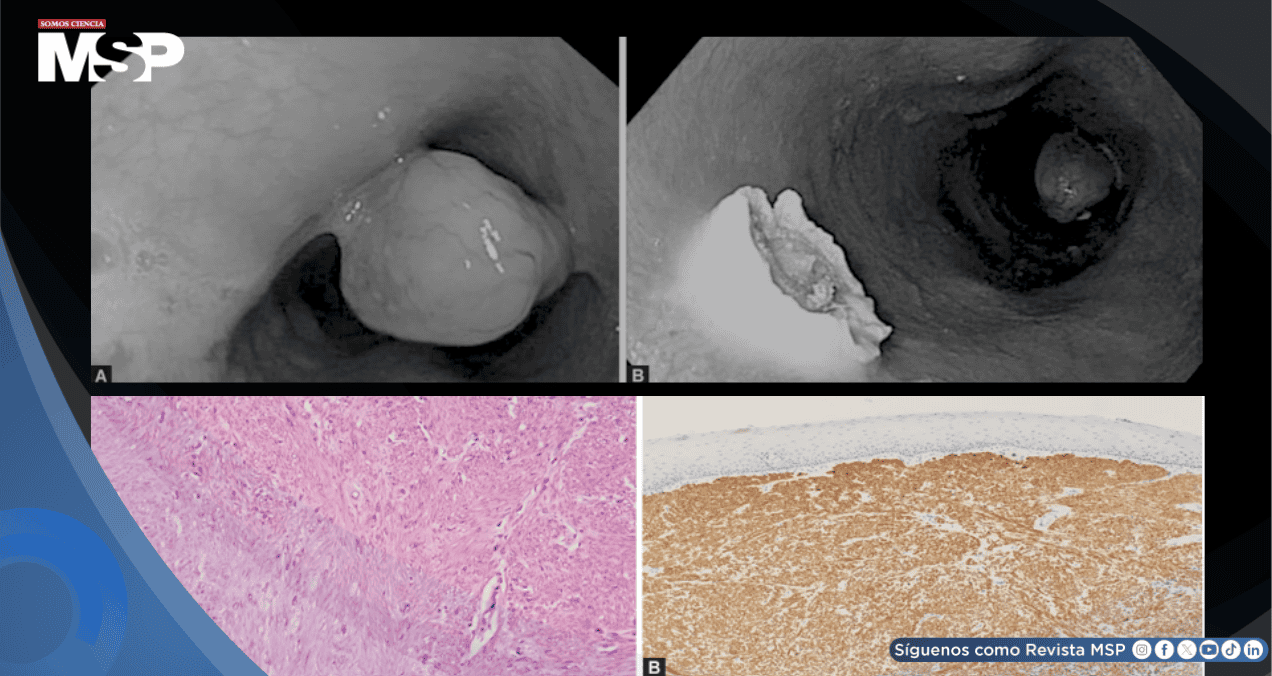

El análisis histopatológico de la cabeza y el pedículo reveló la presencia de un leiomioma esofágico (LE), con tinción positiva para Desmina y anticuerpo anti-músculo liso. Tras la polipectomía, los síntomas de la paciente se resolvieron por completo, con desaparición de la disfagia y mejoría clínica general.